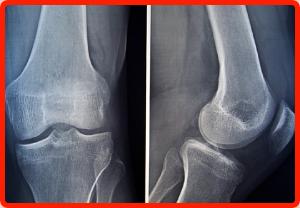

Joint Pain & Arthritis

Joint Pain usually comes from injury, arthritis & wear & tear. This pain signal is our body telling us that it needs help. Ignoring these signals early could cause long-term damage & lead to major surgery. If we follow the CORE ROADS TO LIFE, we make a Commitment to take Ownership of our life. We need to see our doctor, get feedback & do the Research. As a patient, we need to make the best "Joint Decision" with our doctor, caregiver, family & friends.

As the American Academy of Orthopaedic Surgeons (AAOS) states, arthritis simply means "inflammation of the joint." In some forms of arthritis, such as osteoarthritis, inflammation arises because the smooth covering (articular cartilage) on the ends of the bones become damaged or worn. Osteoarthritis is usually found in one, usually weightbearing, joint.

In other forms of arthritis, such as rheumatoid arthritis, the joint lining becomes inflamed as part of a disease process that effects the entire body. Some other types of arthritis are: seronegative spondyloarthropathies, crytalline deposition diseases, and septic arthritis.